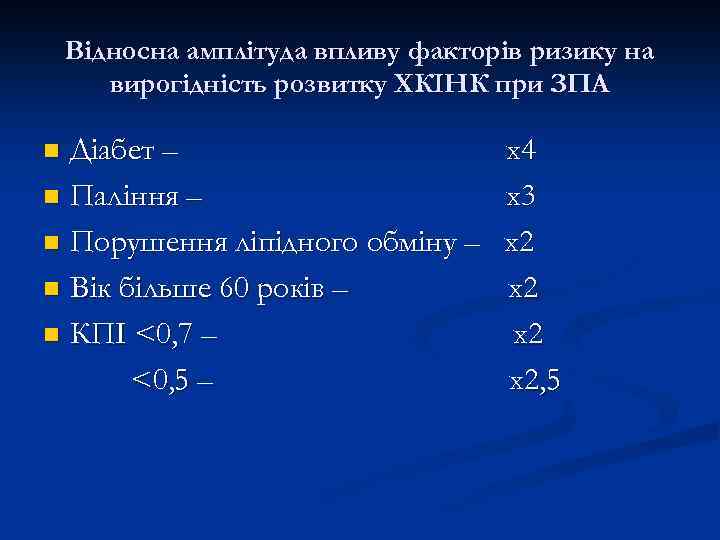

Відносна амплітуда впливу факторів ризику на вирогідність розвитку ХКІНК при ЗПА Діабет – n Паління – n Порушення ліпідного обміну – n Вік більше 60 років – n КПІ <0, 7 – <0, 5 – n х4 х3 х2 х2, 5

Відносна амплітуда впливу факторів ризику на вирогідність розвитку ХКІНК при ЗПА Діабет – n Паління – n Порушення ліпідного обміну – n Вік більше 60 років – n КПІ <0, 7 – <0, 5 – n х4 х3 х2 х2, 5